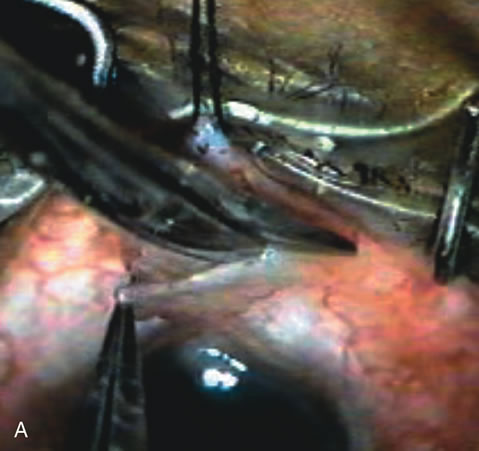

Trabeculectomy Construct the scleral flap, enlarge the wound and insert the IOL (Fig. 17). Instill miochol into the anterior chamber to achieve miosis. Remove the trabecular block and accomplish the peripheral iridectomy (Fig. 18). Some surgeons feel iridectomy may not be necessary;189 however, patients with increased inflammation due to intraoperative complications, uveitis, diabetes, neovascularization, or at increased risk for pupil block require iridectomy.

There is a difference in wound architecture required for insertion of a rigid IOL and closure of a limbus-based conjunctival flap (Fig. 19).

Close the scleral flap and titrate flow (Fig. 20). There are a variety of techniques to gauge flow through the flap. The punch technique is simple especially when used in conjunction with a scleral tunnel. Extend the punch to the end of the tunnel and excise tissue. This functions similar to a valve effect and only one or two sutures are needed to close the flap. Some surgeons prefer an adjustable releasable suture for this step. It is slightly more difficult to titrate flow with this technique.190 If both sides of the scleral flap are opened and a block removed, the valve-like effect is lost and more sutures are necessary to close the flap. This requires more effort and increased surgical time but increases the ability to titrate flow postoperatively.